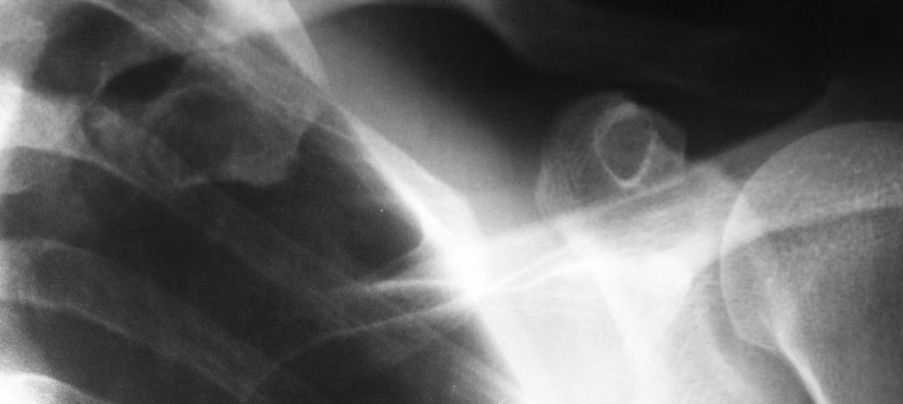

Костная киста первого ребра?

Уважаемые коллеги!Помогите определится с диагнозом и дальнейшей тактикой ведения больного

Пациент 42г,больным себя считает около месяца,когда появились боли при пальпации в области левой подключичной ямки,также беспокоят боли в области правого плечевого и ключино-акромиального сочленений.

Об-но:пастозность в левой подключичной области,боли при пальпации там же,кожные покровы физиологической окраски.При осмотре плечевого сустава -клиника плечелопаточного периартрита.

Приношу извинения за качество рентгенограммы

Посмотрите с другой стороны - вполне возможно, справа 1 ребро точно такое же (так может выглядеть переход костной части ребра в хрящевую).

Если нет, то это может быть:

-кистовидная перестройка грудинного конца ребра дегенеративного или посттравматического характера

-энхондрома

-фиброзная дисплазия

Для диф. диагноза оптимально использовать КТ.

Симптоматичный пациент с очагом ненормальности в 1 ребре на единственном снимке.

Д.д. по снимку - однокамерная киста; энхондрома; эозинофильная гранулома; о.остеома. НО иметь ввиду, что некоторые метастазы могут выглядить сходно.